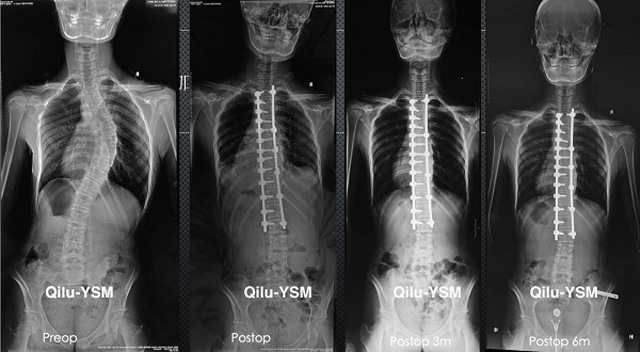

當出現急性外傷或難以控制的慢性疼痛懸吊DR檢查是觀察骨骼簡便的檢查方式,懸吊DR與傳統X線機的區別在于使用相片需要洗片跟數碼存儲數字化,還能進行后期處理分析醫生一般會建議行DR檢查,來判斷是否骨折或者其他情況。 懸吊DR檢查因大大提高了圖像質量,降低了曝光量;成像速度快,工作流程短;圖像動態范圍大;圖像后處理功能強;PACS更強大。適用于人體各部位的健康普查及疾病檢查等優勢,對人體的傷害要更小一個最大的優點,DR的射線量遠小于傳統X線機,在臨床基礎檢查中備受醫生和患者的青睞。

懸吊DR-全電動型機架DR檢查主要用于胸部、四肢、關節、脊柱等,主要檢查肺部炎癥、腫瘤、結核病、四肢骨關節的骨折、四肢關節、脊柱外傷等。DR就是X光,是一種數碼影像,曝光時間很短,攝像量很小,影像質量也很好,可以說是一種替代CR的方法。DR檢查有其局限性,需要做CT平掃等檢查,周圍淋巴結的轉移以確定病變的良惡性、范圍、大小、與鄰近組織的關系。